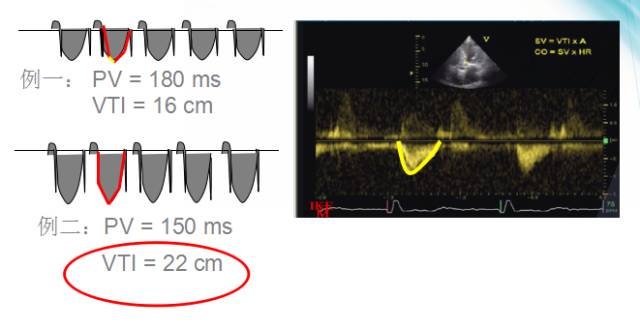

主动脉血流速度时间积分(VTI)

●心室收缩时血流通过主动脉的速率

●与心输出量成一定比例

●“最佳的”SAV/PAV间期能产生最大的VTI值

测量主动脉血流速度时间积分

主动脉血流速度时间积分(AVTI)